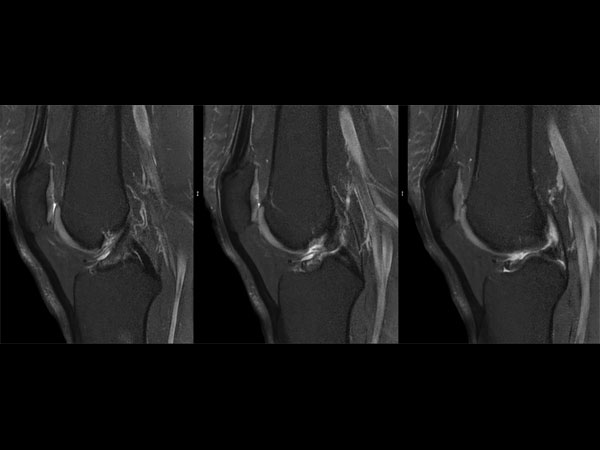

Knee imaging